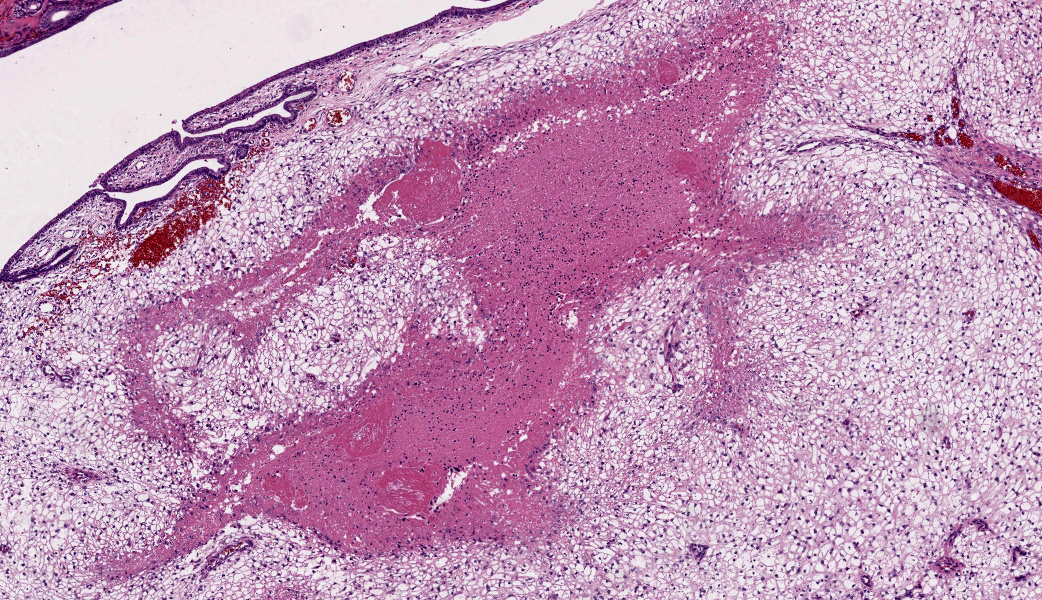

The endometrium on the mesometrial side of the uterus proliferated with the formation of large nodules and numerous polyps. The surface of the nodules and polyps was covered by endometrial epithelium, however, approximately 50% of the epithelium were eroded. The polyps and nodule contained numerous blood vessels with normal endothelium, along with cells that resembled large-vacuolated decidual cells, arranged in sheets. The decidual cells had distinct cell boundaries, a round shape, abundant transparent cytoplasm, and nuclei ranging from oval to irregular shapes. Mitotic figures were also occasionally observed. Just beneath the endometrial epithelium, the decidual cells exhibited a spindle-shaped morphology. (Fig.1 and 2)On the antimesometrial side of the uterine, endometrial hyperplasia was mild, decidual cells in the endometrial stroma were sparse, and proliferation of huge giant cells resembling trophoblast was prominent. The huge giant cells displayed a variety of morphologies, including round, spindle, to pleomorphic, with notably large, highly atypical nuclei and abundant cytoplasm. Multinucleated giant cells were also observed.The immunohistochemical analysis demonstrated that normal endometrial epithelium is positive for progesterone receptor (PgR), keratin AE1/AE3, and CAM5.2, and negative for CD10, SMA and desmin. Normal endometrial stromal cell is positive for PgR and CD10, and negative for keratin AE1/AE3, CAM5.2, SMA and desmin. Decidual cell is positive for PgR and CD10, and negative for keratin AE1/AE3, CAM5.2, SMA and desmin. The huge giant cells exhibited positive for keratin AE1/AE3, CAM5.2 and CD10, and negative staining for PgR, SMA and desmin.

In contrast, numerous giant cells were observed on the obplacental (antimesometrial) region. These giant cells are similar to obplacental giant cells formed in the pregnant uterus of rabbits with regard to both cell morphology and location. 1 The origin of these cells remains unclear. The absence of obvious trophoblasts and the formation of giant cells in the endometrial stroma beneath the normal endometrial epithelium suggest a uterine origin. However, immunostaining revealed positivity for CK and CAM5.2 (epithelial marker) and CD10 (positive for endometrial stromal cell), and negative for PgR (positive for both endometrial epithelial and stromal cell), which did not correspond with the staining patterns of endometrial epithelial or stromal cells. Consequently, it was not possible to ascertain their origin with any degree of certainty.

Uterus, endometrial stroma: Decidual reaction, subacute, focally extensive, severe, with trophoblastic giant cells.JPC Comment: